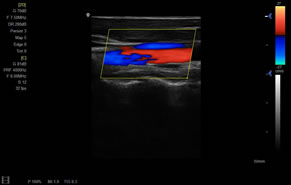

> 彩色血流量圖(CDE)

> 彩色血流分辨增強(qiáng)技術(shù)

廣泛適用于腹部、婦產(chǎn)科、心臟、小器官、乳腺、肌骨及外周血管等諸多方面的診查,讓您在臨床超聲診斷應(yīng)用領(lǐng)域得心應(yīng)手,綻放異彩。